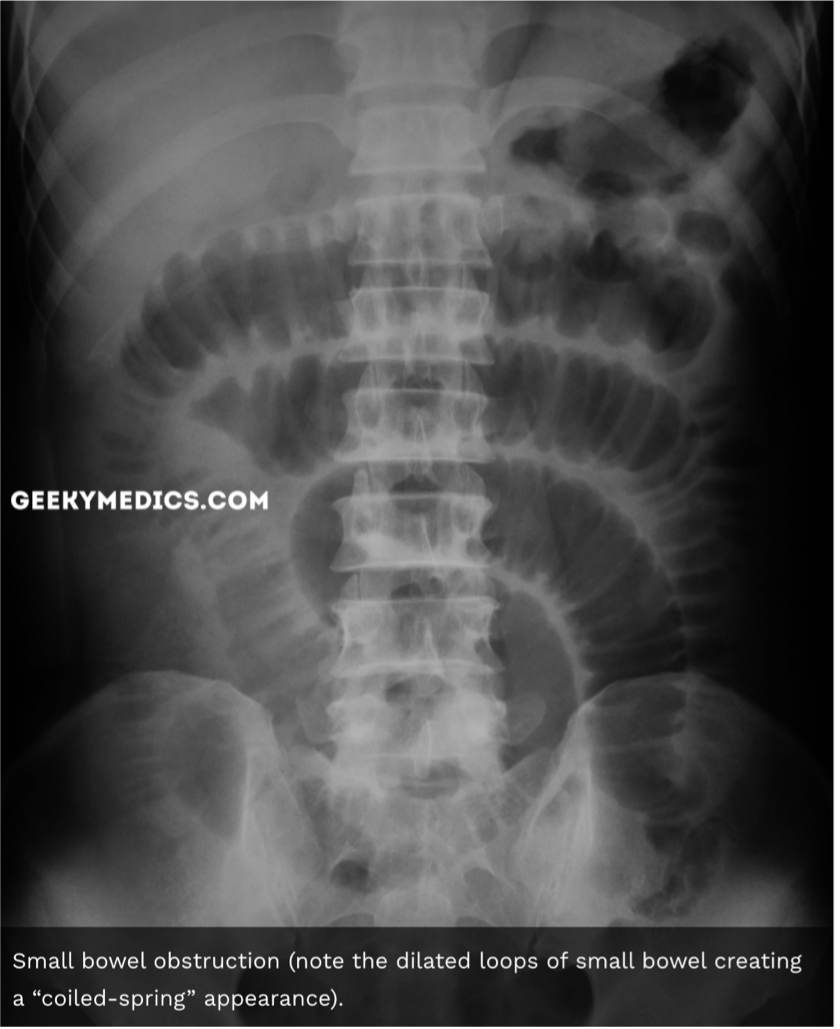

21

Give some AXR features of a SBO

A

• Dilation of small bowel (>3cm diameter)

• Much more prominent valvulae conniventes – create a ‘coiled-spring’appearance